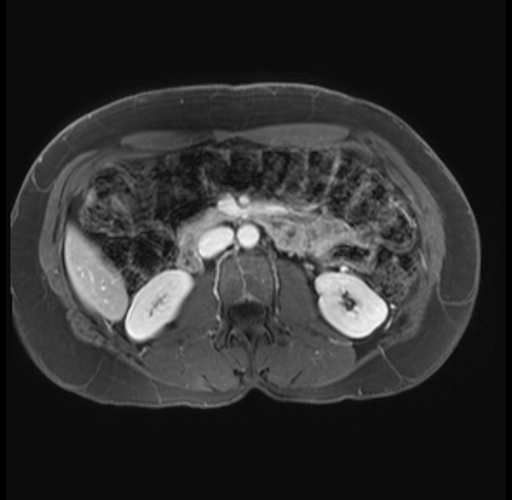

Imaging Analysis

Look through the patient's CT scan to identify any areas of concern for the necessary procedure.

Based on your CT findings, which issue(s) are present and would give reason for "planned slowing down moment(s)" in this case?

Considering a standard distal pancreatectomy procedure, what step(s) of the operation would you do differently in this case?